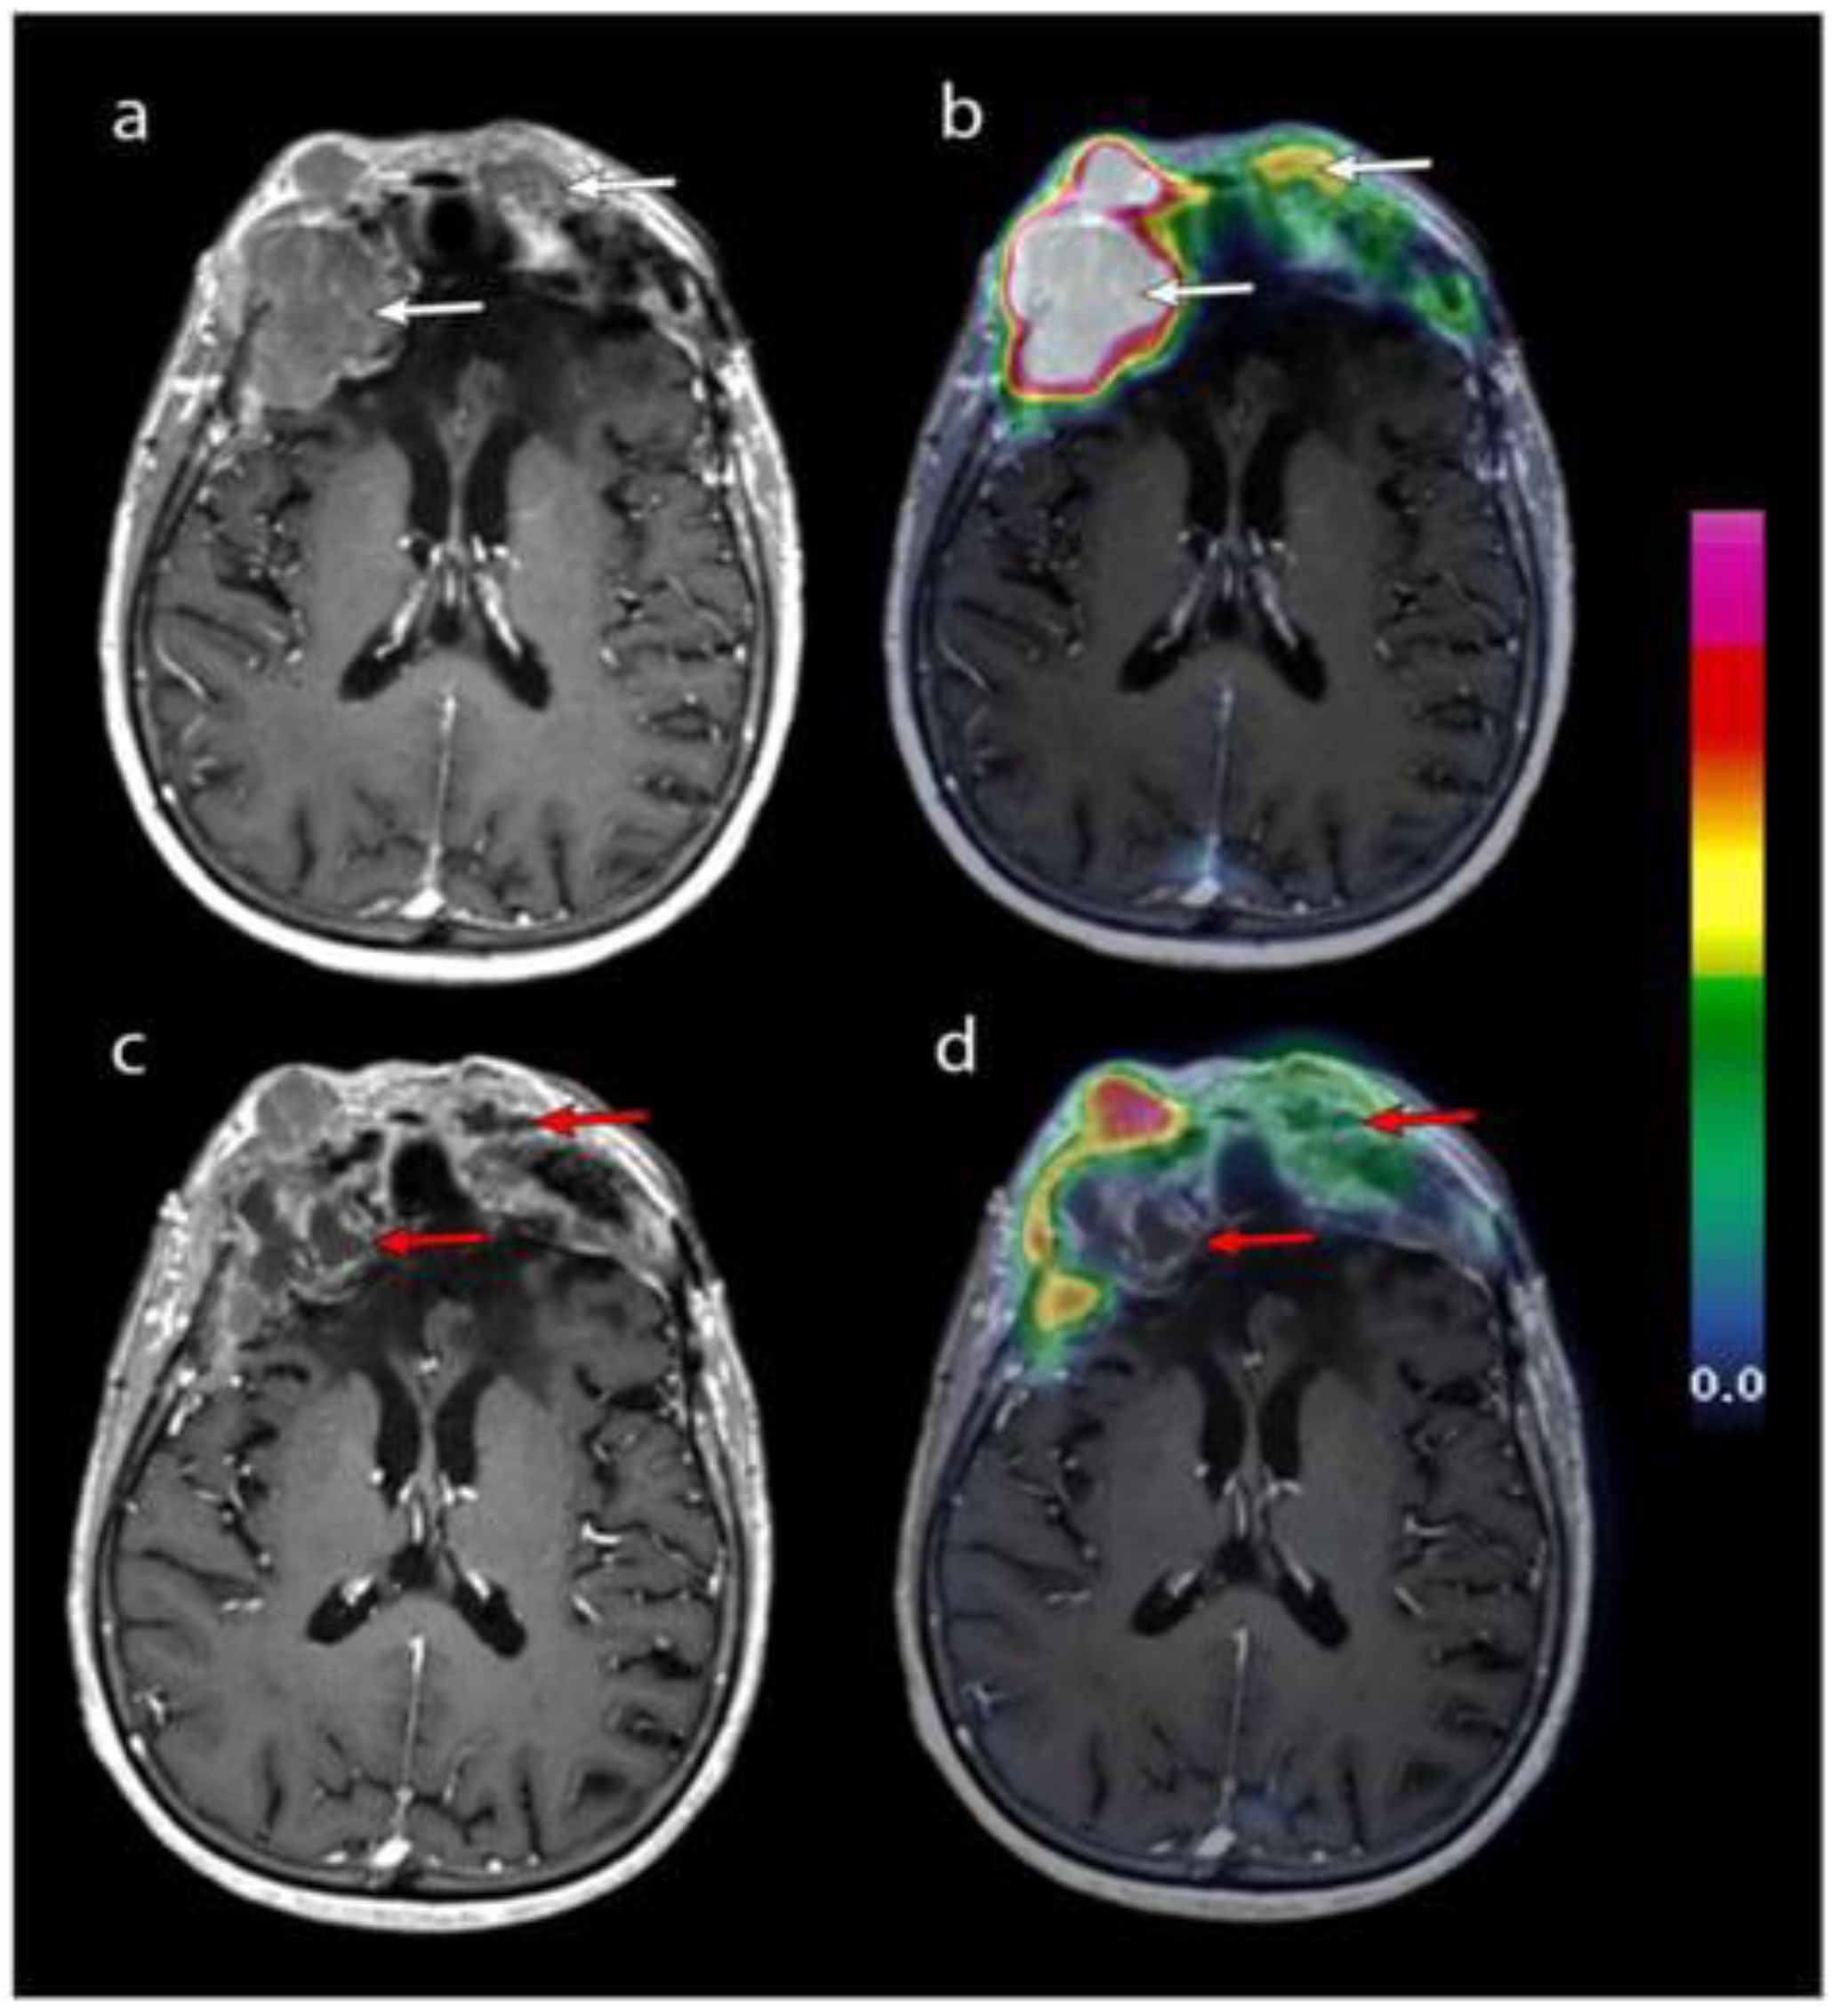

- Ivanidze, J.; Chang, S.J.; Haghdel, A.; Kim, J.T.; Roy Choudhury, A.; Wu, A.; Ramakrishna, R.; Schwartz, T.H.; Cisse, B.; Stieg, P.; et al. [Ga68] DOTATATE PET/MRI-guided radiosurgical treatment planning and response assessment in meningiomas. Neuro Oncol. 2024, 26, 1526–1535. [Google Scholar] [CrossRef] [PubMed]

- Perlow, H.K.; Nalin, A.P.; Handley, D.; Gokun, Y.; Blakaj, D.M.; Beyer, S.J.; Thomas, E.M.; Raval, R.R.; Boulter, D.; Kleefisch, C.; et al. A Prospective Registry Study of 68Ga-DOTATATE PET/CT Incorporation Into Treatment Planning of Intracranial Meningiomas. Int. J. Radiat. Oncol. Biol. Phys. 2024, 118, 979–985. [Google Scholar] [CrossRef] [PubMed]

- Hintz, E.B.; Park, D.J.; Ma, D.; Viswanatha, S.D.; Rini, J.N.; Schulder, M.; Goenka, A. Using 68Ga-DOTATATE PET for Postoperative Radiosurgery and Radiotherapy Planning in Patients with Meningioma: A Case Series. Neurosurgery 2023, 93, 95–101. [Google Scholar] [CrossRef] [PubMed]

| Grade I (WHO) | 17 (18 lesions) | 68Ga-DOTATATE | PET/MRI increased GTV volume vs. MRI (p = 0.008); improved target delineation for radiosurgery. | [26] | |

| Grades I–IV (WHO) | 20 (39 lesions) | 177Lu-DOTATATE | 7.4 GBq/cycle | SUVmean × volume predicted absorbed dose (r = 0.78); optimal threshold: 1.7× meninges SUVpeak. | [44] |